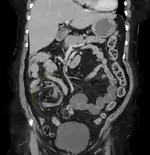

| Coronal CT of the abdomen, demonstrating a volvulus as indicated by twisting of the bowel stock | |

Coffee bean sign in a person with sigmoid volvulus Coronal view of sigmoid volvulus with "whirlpool sign"

Coronal view of sigmoid volvulus with "whirlpool sign".jpg.webp) CT scan of a small bowel volvulus. It shows two juxtaposed segments of narrowing, which is the spot of mesentery rotation. The other signs indicate strangulation.

Plain X ray of a cecal volvulus CT scan of a cecal volvulus

CT scan of a cecal volvulus